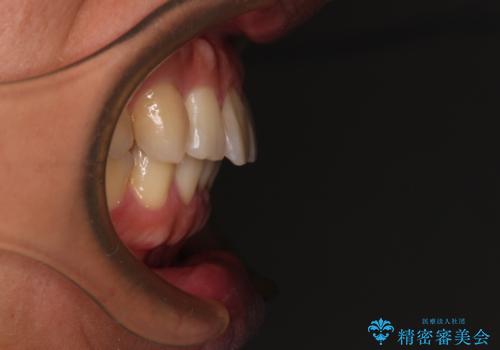

- 前歯のデコボコを気にして来院された患者様です。

当院でインビザライン矯正治療をされている方からのご紹介ということで、インビザラインでの矯正治療をご希望でした。

ワイヤー矯正に比べ来院頻度は低いものの、新幹線での通院のため、やや治療期間が延びることが懸念されました。